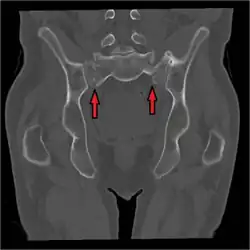

Sacral fracture

A sacral fracture is a break in the sacrum bone.[1] The sacrum is the large triangular bone that forms the last part of the vertebral column from the fusion of the five sacral vertebrae. Sacral fractures are relatively uncommon. They tend to be caused by high-energy trauma, for example in road traffic accidents or in falls.[2]

The Denis Classification System classified sacral fractures into three regions according to the part of the bone affected. The location of the fracture has a major influence on symptoms experienced.[4][5]

- Zone 1 (ala), may cause disruption to the nerve root of the fifth lumbar vertebra (L5)

- Zone 2 (sacral foramina), may cause sciatica

- Zone 3 (sacral canal), may cause cauda equina syndrome